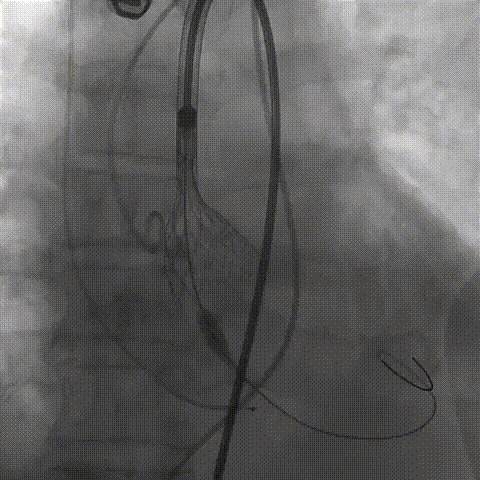

术中影像

根部造影;直头导丝顺利跨瓣

23mm球囊预扩,冠脉显影正常;输送器顺利过弓

初次释放,无冠窦畸形猪尾难以到达窦底,定位带来挑战;释放至工作位,瓣膜(AV29)位置偏低

瓣膜(AV29)完全回收后重新定位释放

瓣膜(AV29)工作位正交体位造影位置良好,左冠显影正常

瓣膜(AV29)完全脱钩释放后23mm球囊充分后扩,冠脉灌注良好

最后造影

术后血流动力学

瓣膜工作状态良好,极微量瓣周漏,血流动力学有效改善